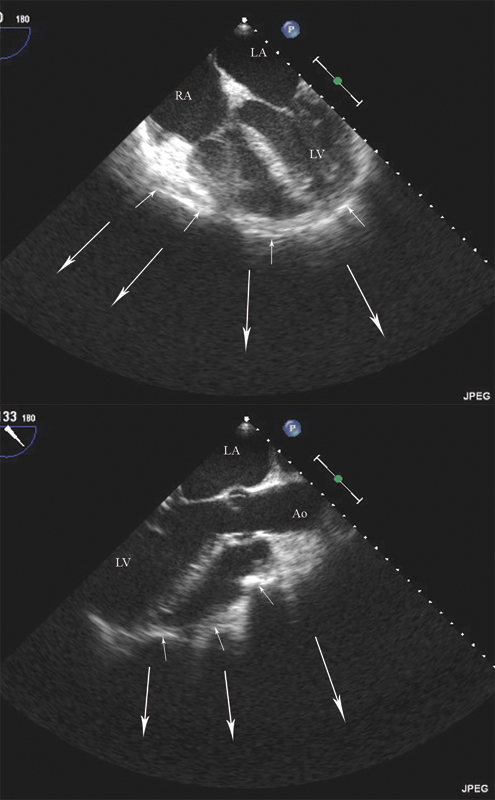

فحوصات تشخيصية لبعض امراض القلب والشرايين التاجية